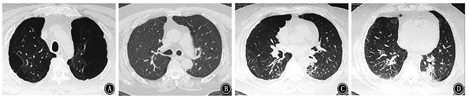

患者男,64岁,因"反复咳嗽、咳痰、喘憋18年,加重20余天"于2018年1月26日入院。患者近18年反复出现咳嗽、咳痰、喘憋,诊断为COPD、肺气肿、肺大疱、矽肺Ⅰ期等。近3年因COPD急性加重多次住院,经抗感染、化痰、平喘等治疗可好转,院外长期吸入沙美特罗替卡松粉(舒利迭)、噻托溴铵粉(思力华),口服止咳、化痰药物。2018年1月3日患者受凉后再次出现咳嗽、咳痰、喘憋加重,就诊于北京某医院。2018年1月3日胸部CT示两肺见多发粗大索条影,边缘模糊,肺气肿,多发肺大疱,左肺下叶球形肺不张,双侧胸膜肥厚,右侧胸膜钙化,右肺下叶支气管扩张(图1),考虑肺部感染。住院后给予哌拉西林舒巴坦钠、比阿培南、莫西沙星等抗感染,并给予甲泼尼龙抗炎(具体不详)。患者病情好转,于2018年1月24日出院。出院后按医嘱继续口服醋酸泼尼松40 mg/d。2018年1月26日患者出现发热,体温最高达38 ℃,咳嗽、咳痰、憋喘较前加重,安静状态憋喘,咳痰带鲜红血丝,伴纳差、乏力,无盗汗,无胸痛,无头晕、恶心,来北京老年医院急诊就诊。血常规:白细胞计数23.69×109/L,红细胞计数5.42×1012/L,血红蛋白158 g/L,血小板计数173×109/L,中性粒细胞比例87.3%,淋巴细胞比例5.7%;血气分析:pH值7.45,PaCO2为41.4 mmHg(1 mmHg=0.133 kPa),PaO2为72.2 mmHg,SaO2为94.5%;血凝指标、D-二聚体、肌钙蛋白I、肌酸激酶同功酶、B型钠酸肽均正常。2018年1月26日胸部CT与2018年1月3日比较,双肺新出现散在斑片影及斑点影,伴大小不等空洞,部分空洞周围可见晕征(图2),考虑双肺感染进展,收住北京老年医院呼吸康复科。